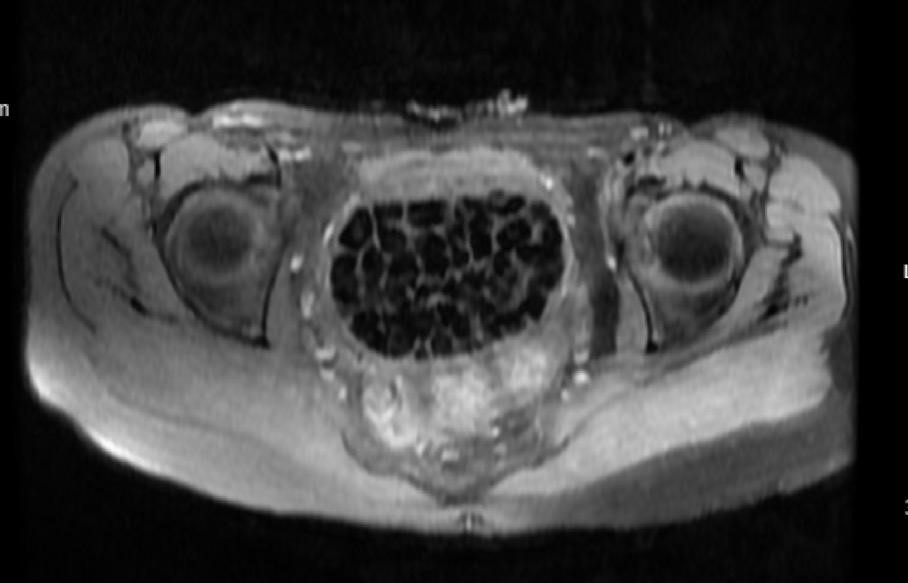

11 Eylül'de gerçekleştirilen operasyon sırasında doktorlar da beklemedikleri bir manzarayla karşılaştı. Ameliyatta mesanenin vajene açıldığı bir fistül olduğunu gören ekipler, tüm vajen boşluğunun taşlarla dolu olduğunu fark etti. Uzmanlar, en büyüğü 2,5 cm boyutunda olan irili ufaklı 287 adet taşı başarılı bir operasyonla çıkardı. Taşların sayısını duyan Fatma Nur ve ailesi büyük bir şaşkınlık yaşarken, ağrıları dinen genç kız operasyonun ardından rahat bir nefes aldı.

Operasyonu gerçekleştiren doktorlardan Doç. Dr. Erkan Erkan ve Op. Dr. Emin Erhan Dönmez, bu vakanın literatürde çok nadir görülen bir durum olduğunu belirtti. Doç. Dr. Erkan, "Bu kadar çok sayıda taşı beklemiyorduk. Bu, dünyada bu tanıma uyan ikinci vaka olabilir" dedi. Op. Dr. Dönmez ise taşların, doğumsal anomali nedeniyle idrarın vajen boşluğunda birikmesi ve minerallerin çökelmesi sonucu oluştuğunu düşündüklerini ifade etti.